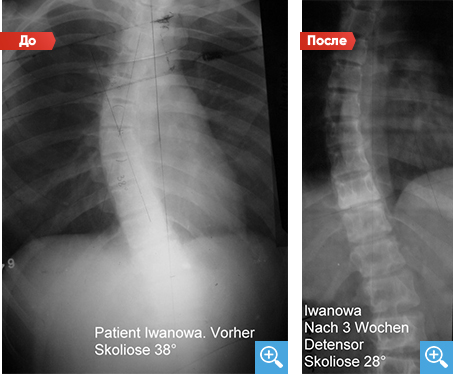

результаты лечения

Сколиоз

После проведения 3 недель Детензор-терапии по 45 минут 4 раза в день отмечено уменьшение степени сколиоза: с 3-ей степени 38° до 2-ой степени 28°, увеличение межпозвонковых дисков.